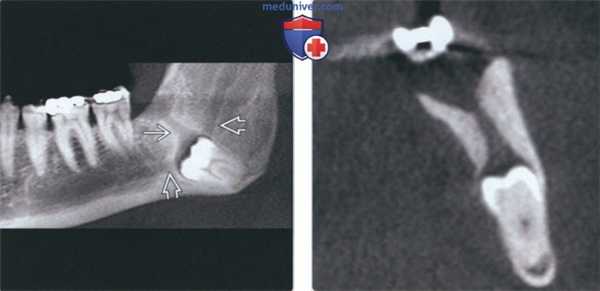

(Слева) На кадрированной панорамной реформатированной КЛКТ визуализируется импактный третий моляр в области угла нижней челюсти. Четко визуализируется ПЗ, связанный с верхним краем фолликула. ПЗ рассматривается как тракт, по которому зуб проходит к обычному месту прорезывания в альвеолярном отростке. Обратите внимание на сдавление нижнечелюстного канала снизу.

(Справа) На профильном срезе КЛКТ у этого же пациента визуализируется проводник зуба.